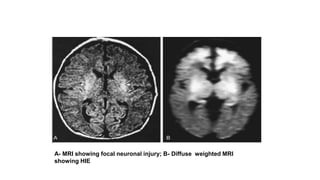

MRI is the preferred imaging modality in neonates

with HIE

CT scans are helpful in identifying focal hemorrhagic lesions, diffuse

cortical injury, and damage to the basal ganglia;

CT has limited ability to identify cortical injury during the 1st few days of

life.

Ultrasonography has limited utility in evaluation of hypoxic injury in the

term infant; it is the preferred modality in evaluation of the preterm

infant.

A- MRI showing focal neuronal injury; B- Diffuse weighted MRI

showing HIE